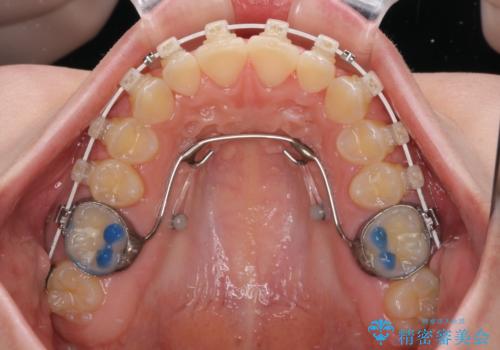

- 矯正装置

- 審美装置

短期間で確実に仕上げたいとのことで、アンカースクリューと補助装置を併用して歯列の後方移動を図り、ワイヤー装置にて矯正治療を行うこととしました。

左上の歯列は補助装置により速やかに移動し、1年程度で奥歯の咬み合わせが改善され、1年3ヶ月の短期間でしっかりと仕上げることができました。